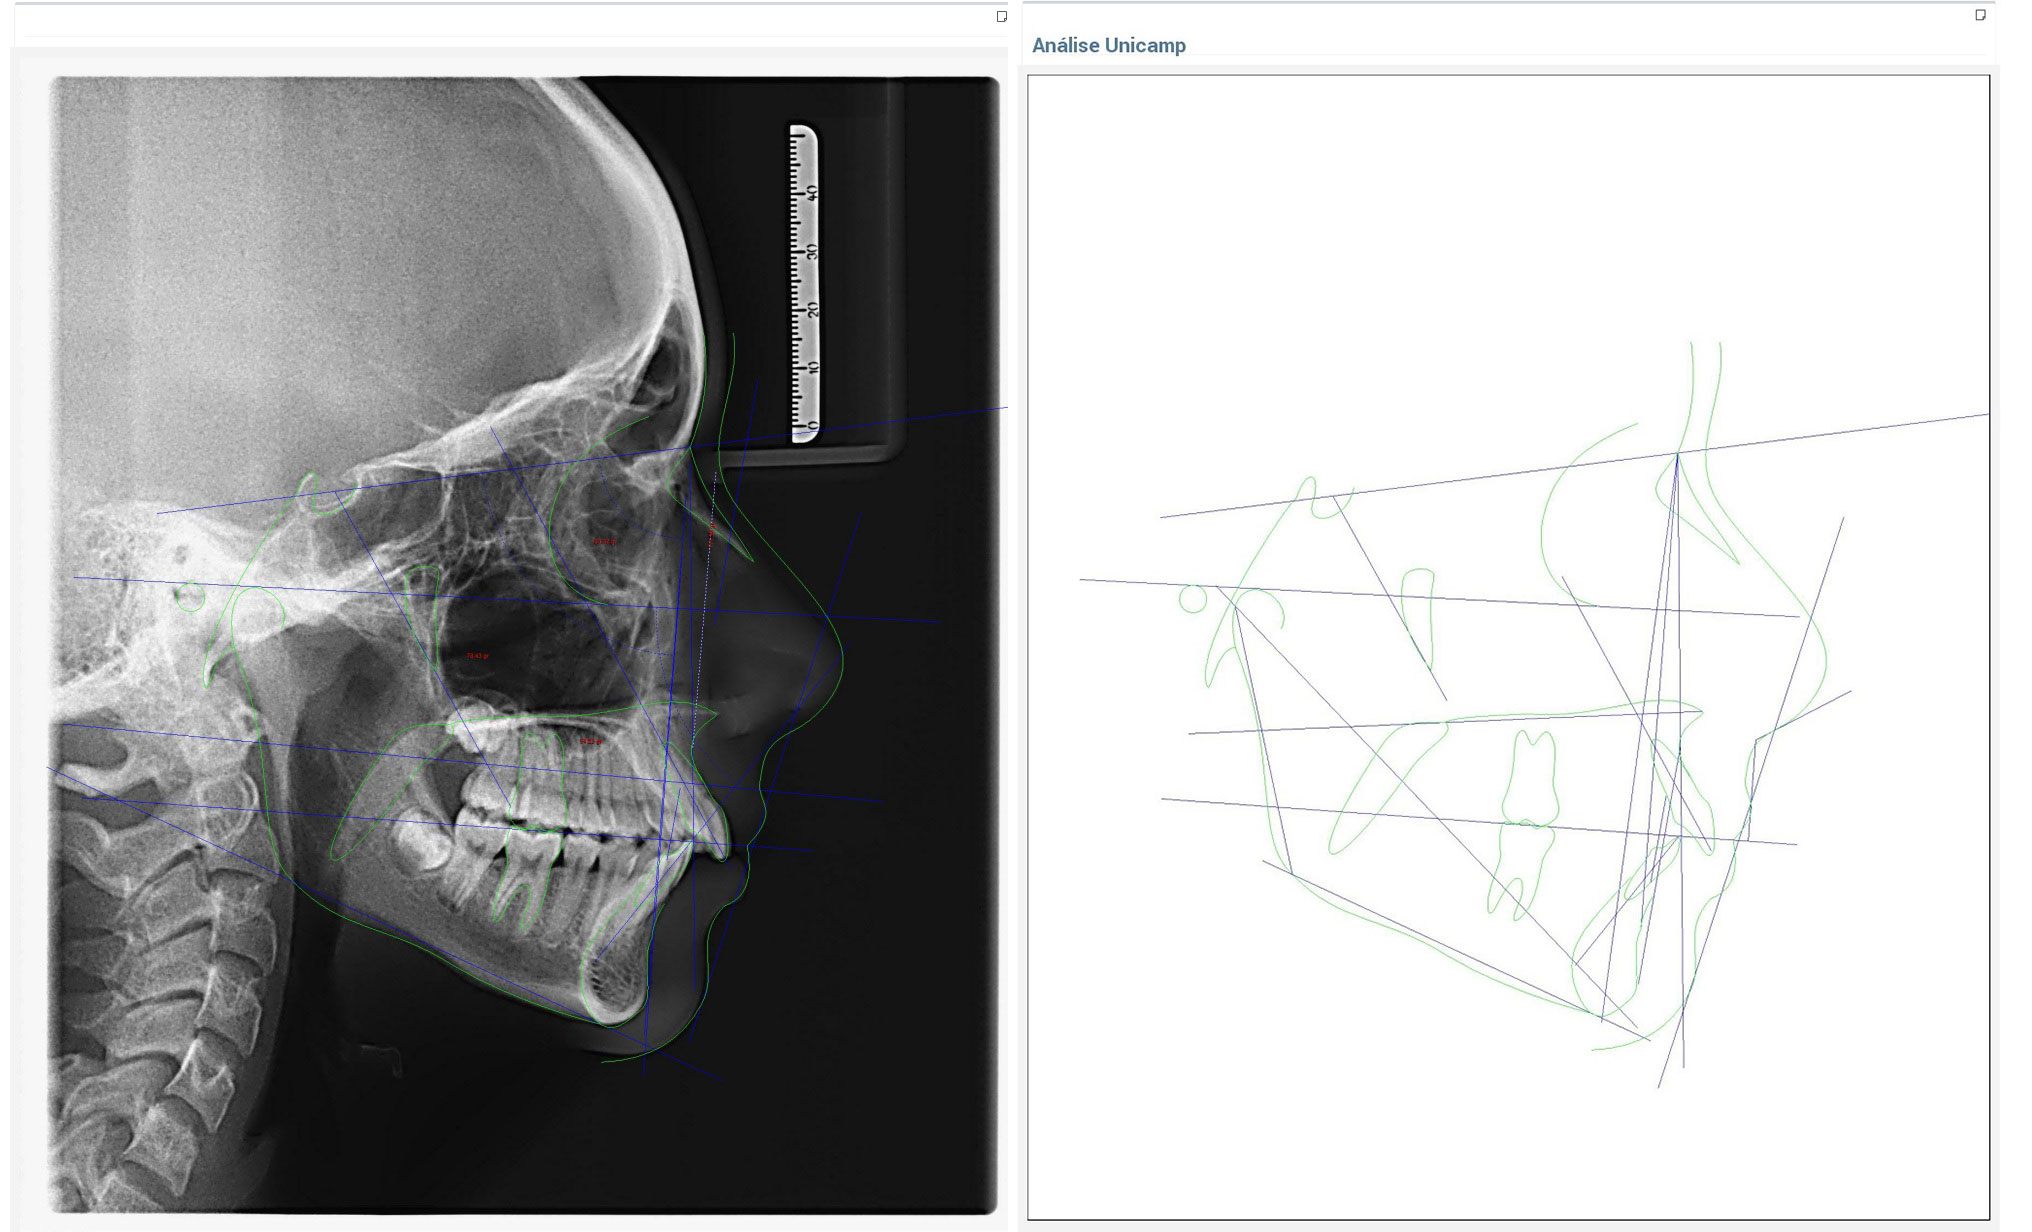

- Telerradiografia

Documentações